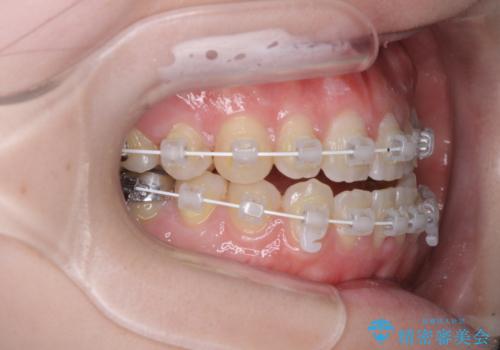

- 矯正装置

- 審美装置

骨格のズレと歯の欠損があったため、仕上がりの調整に時間がかかると思いましたが、舌突出癖の改善や顎間ゴムの装着をしっかりと行ってくださったので、速やかに治療を終えることができました。